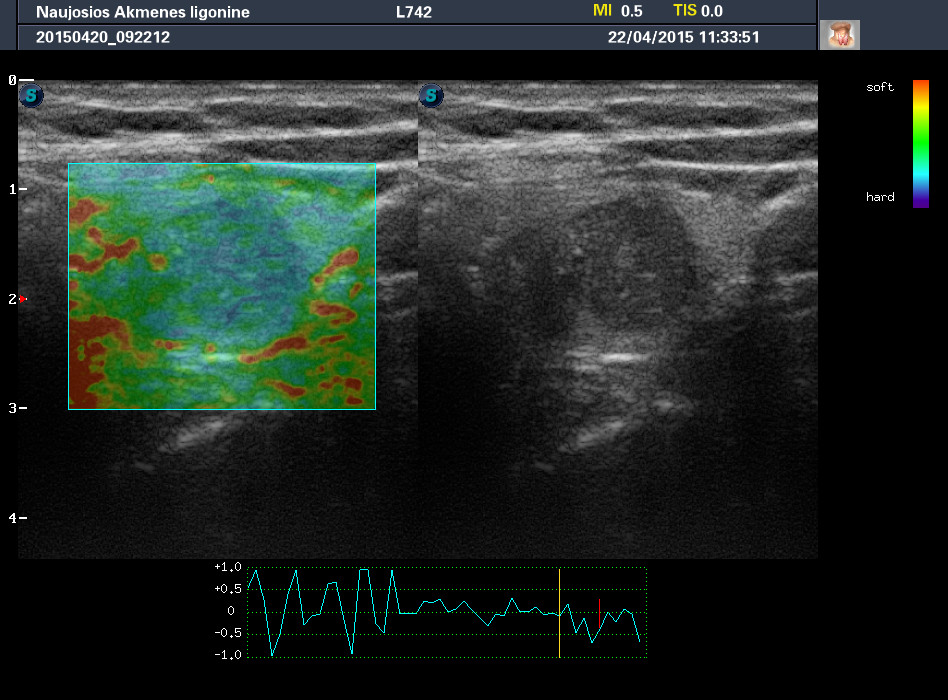

Случай 1

Женщина 67 лет, жалоб нет. Рост узла за год +3 мм. Регионарные ЛУ не увеличены.

apr222015072652_0.jpg

apr222015073251_8.jpg

1-й узел злокачественный, а 2-й ,скорее всего, доброкачественный. Но,понятное дело, нужна пункция и было бы здорово узнать результат.

Цитология 1 случая - злокачественных клеток не обнаружено.

Обычно фолликулярный эпителий, кровь, коллоид.

Но в данном конкретном случае ответ был именно таким - "злокачественных клеток не обнаружено".